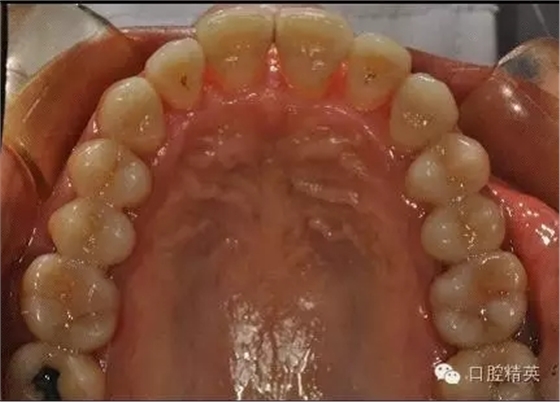

治療前: